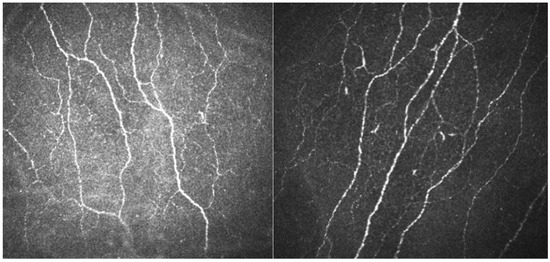

- Lukashenko, M.V.; Gavrilova, N.Y.; Bregovskaya, A.V.; Soprun, L.A.; Churilov, L.P.; Petropoulos, I.N.; Malik, R.A.; Shoenfeld, Y. Corneal Confocal Microscopy in the Diagnosis of Small Fiber Neuropathy: Faster, Easier, and More Efficient than Skin Biopsy? Pathophysiology 2021, 29, 1–8. [Google Scholar] [CrossRef]

| CNFD, Corneal Nerve Fiber Density | CNBD, Corneal Nerve Branch Density | CNFL, Corneal Nerve Fiber Length | |

|---|---|---|---|

| Patient’s results | 29.86 | 49.30 | 18.79 |

| Normal median values for 36–45 years, female [35] | 28.56 | 63.27 | 23.28 |

| Normal 5th quartile for 36–45 years, female [35] | 14.79 | 18.19 | 12.48 |